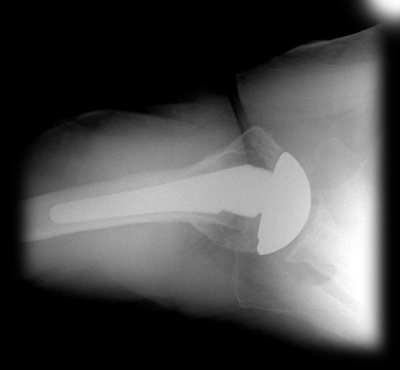

The Univers II humeral component was designed to account for anatomical variations of the proximal humerus commonly encountered by the surgeon. Variable adjustment with respect to the inclination angle, version and head offset are features critical to reconstruction of the proximal humerus. The simplified design of the Univers II humeral component allows the surgeon to adapt the humeral stem and articular surface to the position that best represents the patient’s normal anatomy. All of the adjustments can be made intraoperatively with the implant in the humeral canal. This unique feature allows more accurate recreation of the normal anatomical relationships of the shoulder joint. With anatomic restoration of the humerus and glenoid, soft tissue balancing of the rotator cuff is more accurate, allowing for improved functional outcome.